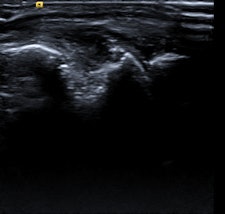

In the 12-page article, the authors outline the role of imaging -- in particular radiography, MRI, CT, ultrasound, and nuclear medicine-- for the diagnosis and monitoring of rheumatological disorders, concentrating on rheumatoid arthritis, inflammatory spondylarthropathies, and gout.

Radiographs might show evidence of bone erosion and/or other reactive bone change with ankylosis of the spine, the most extreme form of reactive bone change, according to Tins and Butler. While it is important to note these findings and suggest the diagnosis if unsuspected, radiographs are of limited value in the diagnosis of early inflammatory spondyloarthropathy because of the high false-negative rate. To an even greater extent than in rheumatoid arthritis, the radiographic changes often lag behind the clinical presentation by years, they pointed out.

"Nevertheless, rheumatologists in the U.K. often request plain x-rays because the current U.K. NICE (National Institute for Health and Care Excellence) criteria for the use of TNF (tumor necrosis factor) inhibitors in ankylosing spondylitis require that the patient fulfills the modified New York radiographic criteria. While CT is more sensitive for reactive bone change, it is insensitive for edema-like change of bone marrow or soft tissues and MRI is preferred for this," they stated.